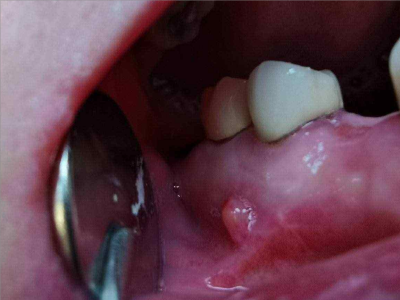

慢性龈炎又称边缘性龈炎或单纯性龈炎,主要表现为游离龈和龈乳头因炎性水肿,而变为鲜红或暗红色,龈缘变厚,龈乳头圆钝肥大。慢性龈炎的患病率高,治愈后仍可复发,部分患者可发展成为牙周炎。

慢性龈炎的病损部位一般局限于游离龈和龈乳头,以前牙区为主,尤其以下前牙区最为显著,患者常因刷牙或咬硬物时牙龈出血而就诊。游离龈和龈乳头颜色变为鲜红或暗红色,病变较重时炎性充血可波及附着龈。龈缘变厚,龈乳头圆钝肥大,可增生呈球状,覆盖牙面。牙龈松软脆弱,缺乏弹性。

当牙龈以增生性反应为主时,龈缘和龈乳头呈坚韧的实质性肥大,质地较硬而有弹性。龈沟液量增多,还可能出现龈沟溢脓现象。